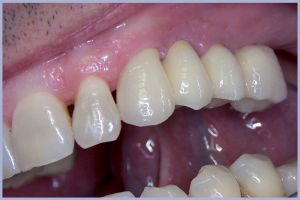

- Figg. 10, 11 – Consegna

- Figg. 21, 22 – Visione intraorale del manufatto protesico definitivo